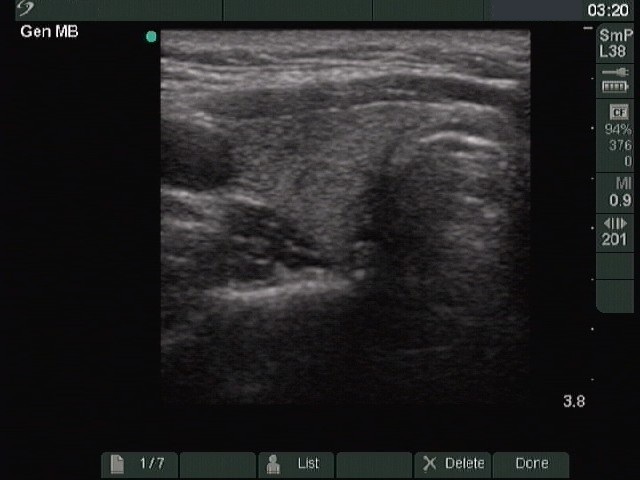

Ultrasonography. The right lobe was intact, while the left was composed of a large nodular area with multiple hypoechogenic and hyperechogenic discrete lesions. The latter corresponded to necrosis.